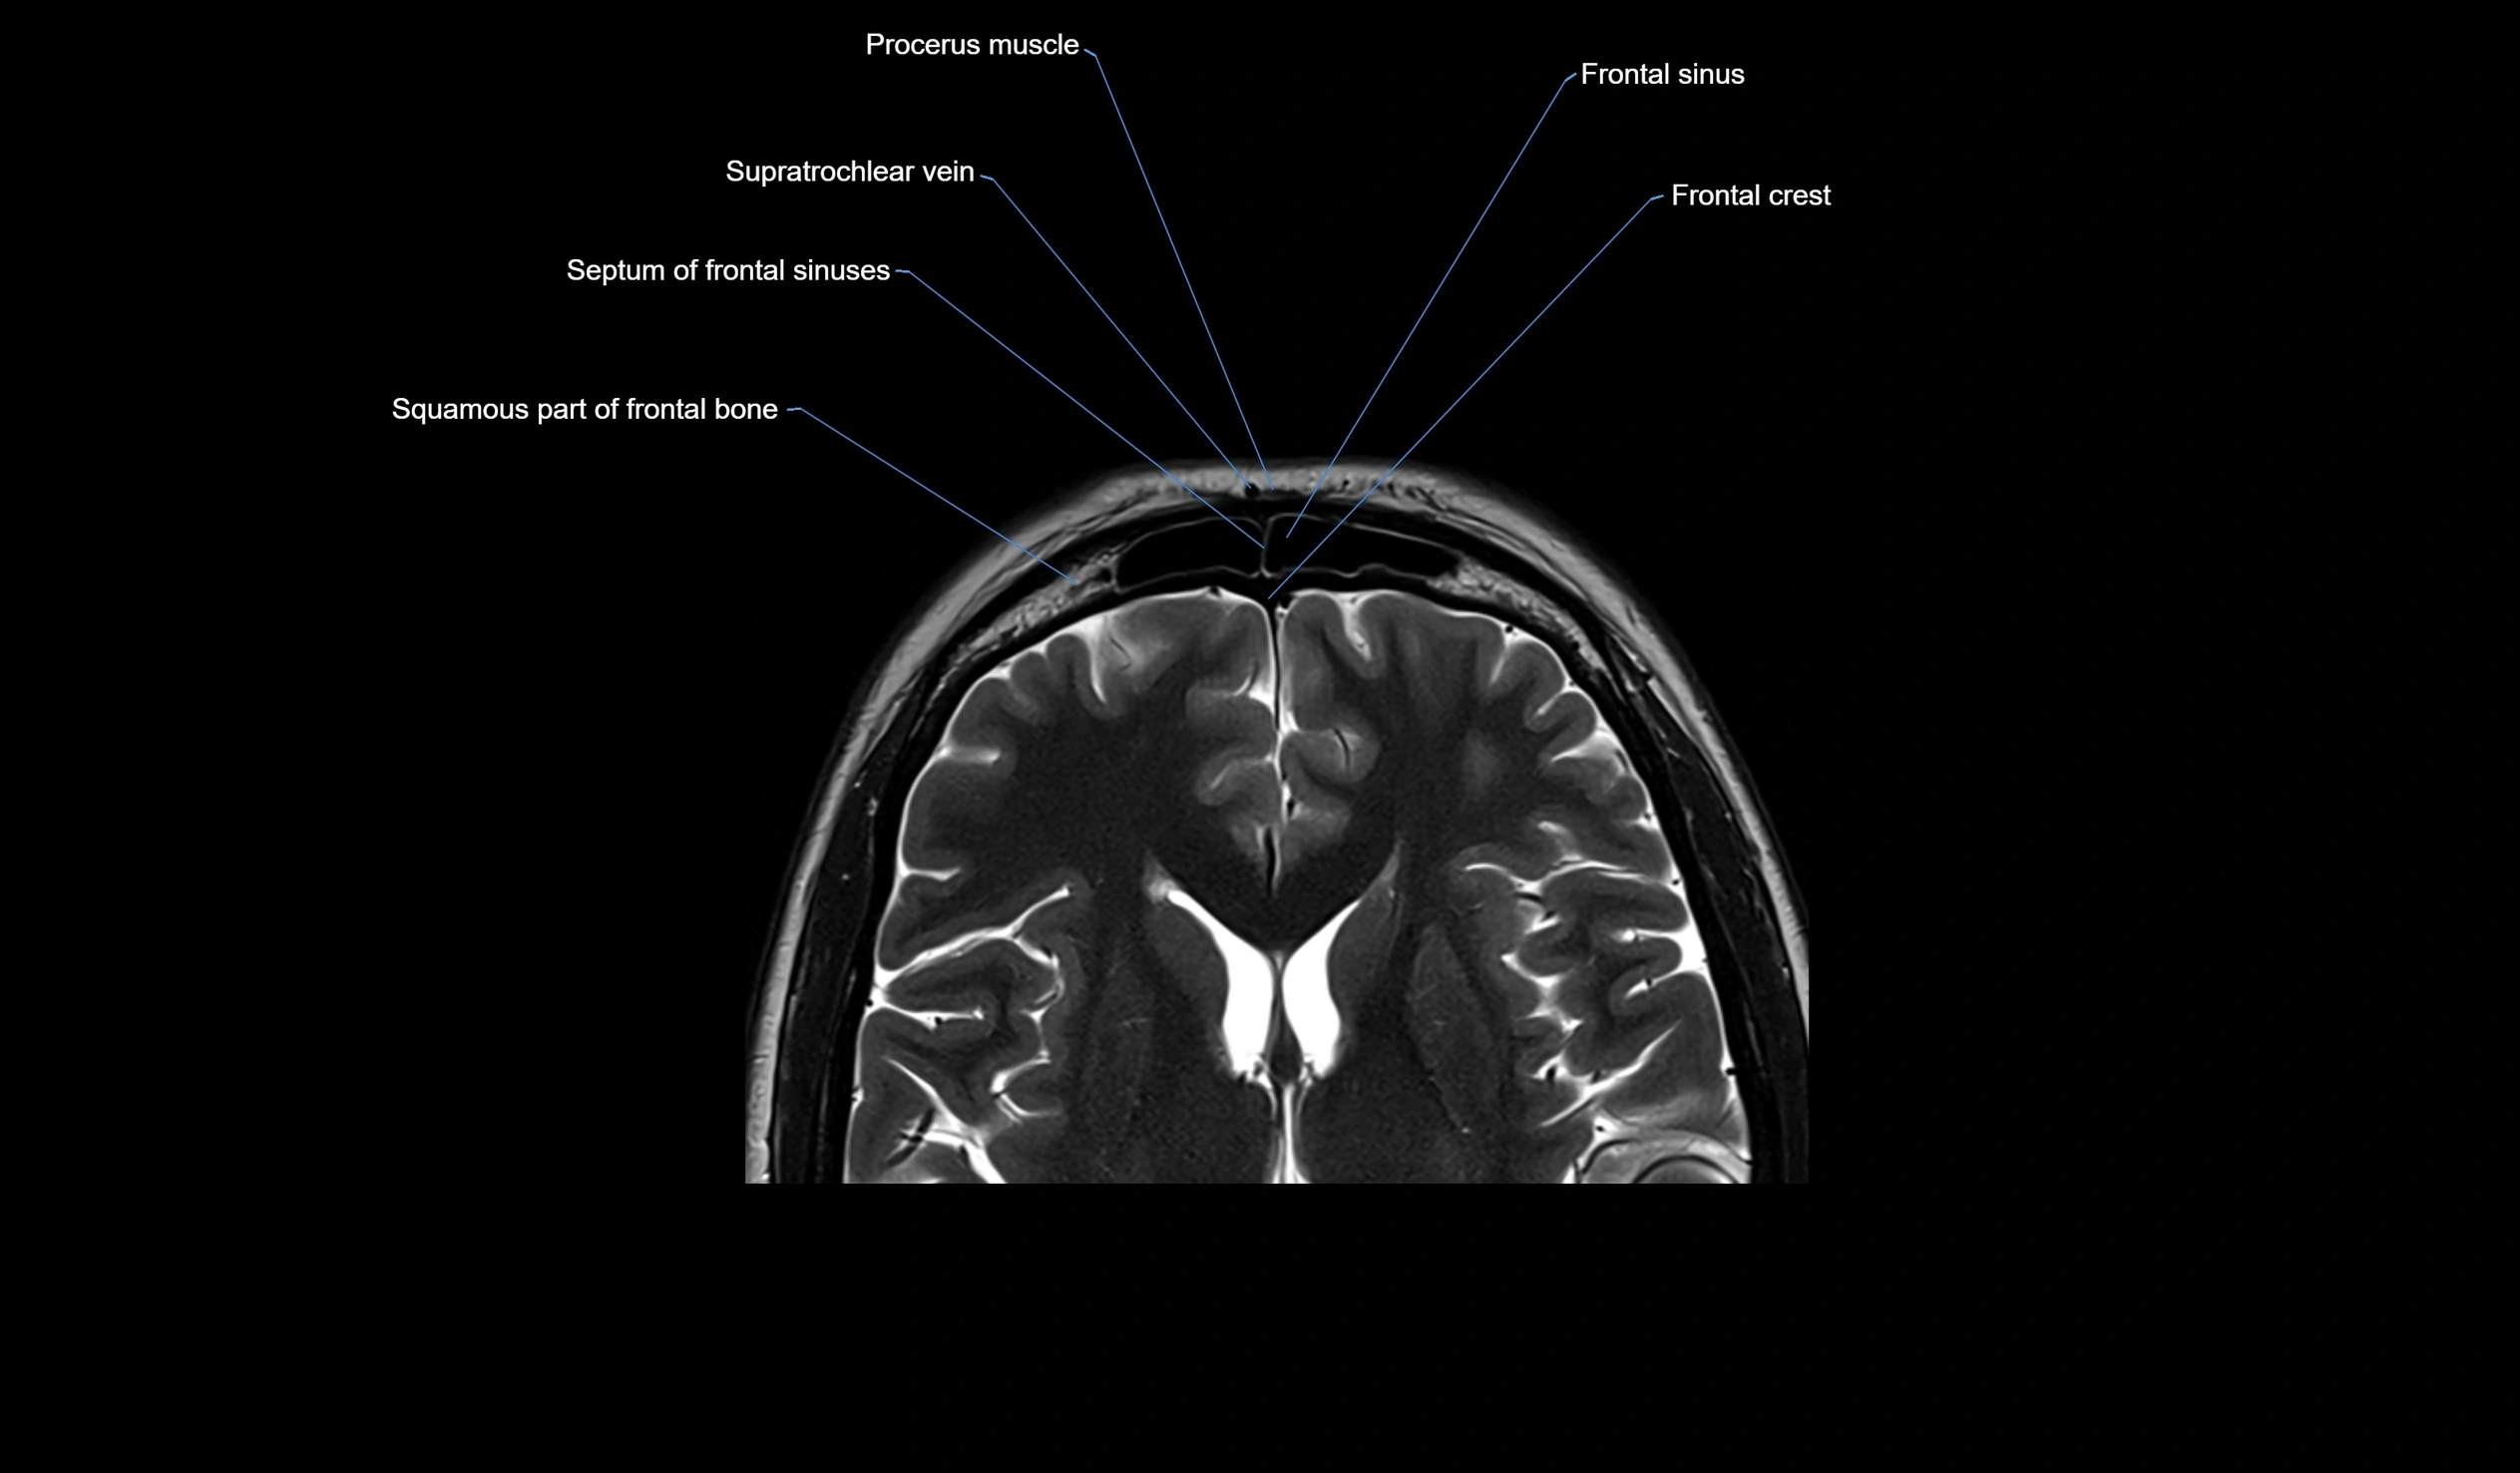

MRI images